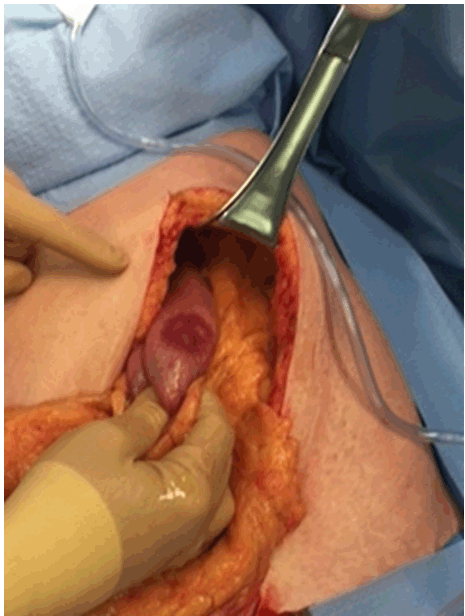

During surgical exploration (Figure 2), many lymph nodes were noted in the mesentery of the proximal jejunum. Two gastric lesions were found in the body of the stomach (Figure 3). In addition, the involved segment of jejunum was resected and two lesions were found, very similar in appearance to the ones in the stomach. A subtotal gastrectomy with Roux-en-Y anastomosis was performed following the segmental jejunal resection. The margins of resection were 5 cm, as recommended for a gastric adenocarcinoma. Finally, immediate post-operative course was favorable and the patient has been well 2 months after operation. Close follow-up of the patient is still undergoing.

Figure 2: Intraoperative presentation of one of the ulcerated lesions of the stomach.